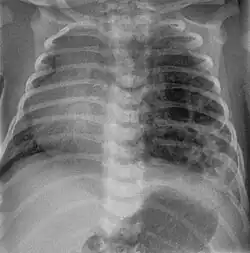

Tension pneumothorax

Tension pneumothorax is an emergent condition in which air gets trapped in the space between the chest wall and the lung. This space is referred to as the pleural space. Because air can't escape from this space, the air pocket grows larger and larger, resulting in the lung collapse closest to the pneumothorax. Forces are transmitted to the mediastinum and effectively "push" the mediastinal structures to the opposite side of the chest.[5]